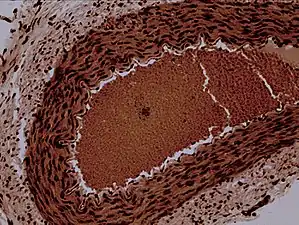

![]() Rabbit arteriole at 100X | |

Arterioles have muscular walls (usually only one to two layers of smooth muscle) and are the primary site of vascular resistance. The greatest change in blood pressure and velocity of blood flow occurs at the transition of arterioles to capillaries.

Microanatomy

In a healthy vascular system the endothelium lines all blood-contacting surfaces, including arteries, arterioles, veins, venules, capillaries, and heart chambers. This healthy condition is promoted by the ample production of nitric oxide by the endothelium, which requires a biochemical reaction regulated by a complex balance of polyphenols, various nitric oxide synthase enzymes and L-arginine. In addition there is direct electrical and chemical communication via gap junctions between the endothelial cells and the vascular smooth muscle.